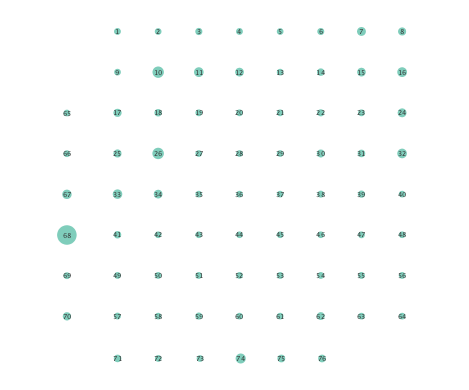

Clustering coefficients are generally used to quantify network cohesion, the tendency for nodes to form groups or communities. Comparison of such coefficients between the preictal and ictal phases may reveal differences in cohesive behavior after onset of a seizure. In the present paper, a per-node clustering coefficient is adopted, and it computes the fraction of triangles in which a node participates out of all possible triangles to which it could possibly belong [24]. Note that a triangle is defined as a fully connected three-node subgraph. Figure 5 depicts clustering coefficients per electrode obtained during the ictal and preictal phases of the ECoG time series. While both the linear and nonlinear models yield changes in the computed coefficients, most nodes have lower clustering coefficients upon seizure onset in the networks inferred via the K-SVARM.